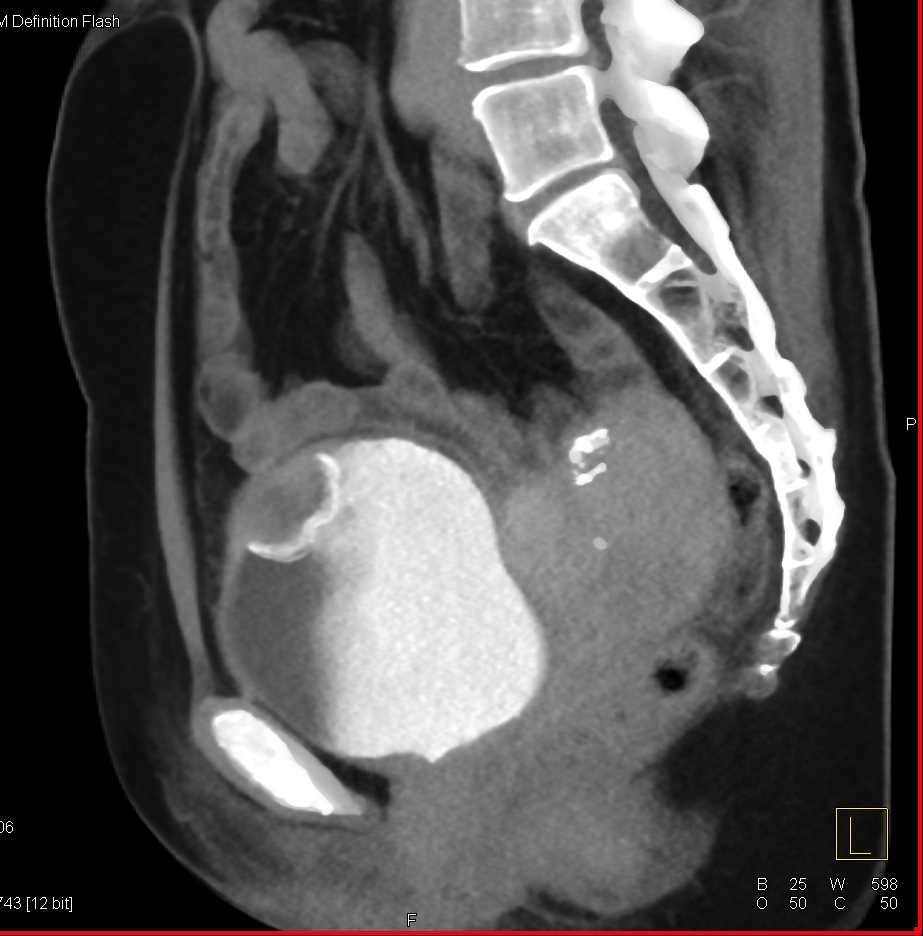

Urachal Carcinoma of the Bladder